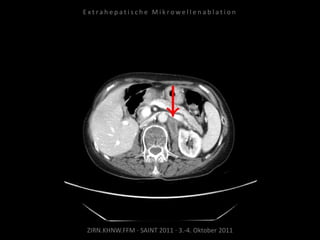

Patient: Weiblich, 71 Jahre

Diagnose: Ovarial-Ca,

größenprogredienter Lymphknoten

zwischen Herz und Leber als einzige

Metastase.

Bildgebung vor MWA:

CT 14.03.2011

Situation:

Nur 1 Metastase, diese ist jedoch

progredient. Kritische Lage in

Herznähe.

Ablation am 24.03.2010:

2 Nadelpositionen.